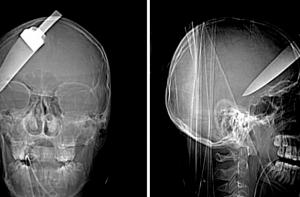

На Сальвадоре врачи одного из частных госпиталей провели операцию по удалению лезвия ножа длинной в 10 сантиметров из головы человека. Мужчина прожил с этим инородным предметом в черепе более 17 лет.

В1995 году местный сапожник по имени Хорхе Альберто Гонсалес Кампос пережил нападение преступников-токсикоманов, которые хотели отобрать у него сапожный клей. Однако мужчина начал драку, в результате которой получил ножевое ранение в голову. Вплоть до 2007 года жертва нападения даже не подозревал о том, что лезвие ножа осталось внутри его черепа, сообщает РИА «Новости».

Сапожник обратился к врачам из-за частых головных болей. Выяснив, что в организме мужчины началось отторжение инородного предмета, медики отправили его на операцию, которая состоялась только через шесть лет, после того, как на это решились хирурги одного из частных госпиталей.

Десять опытных специалистов под руководством нейрохирурга Эдуарда Лово занимались извлечением осколка. Операция продолжалась в течение семи часов и завершилась успешно. Пациент уже пришёл в себя и может говорить. Все расходы на лечение Кампоса оплатит частный фонд, уточняет Utro.ru.